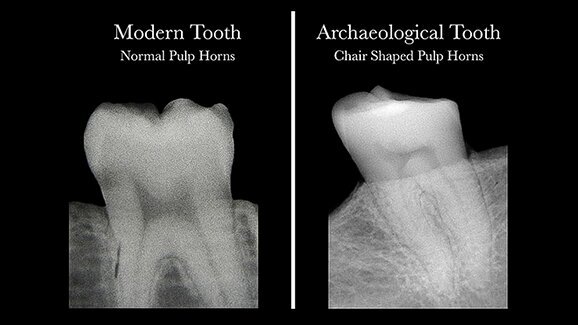

To avoid wasting precious specimens, the researchers looked for a way to isolate teeth for further investigation. By using radiographs to study the readily observable shapes of the pulp horns, the researchers found a consistent, recognizable pattern that could prove helpful both to their studies of archaeological teeth, as well as to people who may not realize they are suffering from vitamin D deficiency.

The pulp shape in a healthy person’s tooth resembles an arch topped by two cat ears, but in a person who has had a severe deficiency of Vitamin D is asymmetrical and constricted, typically looking like the profile of a hard-backed chair.

D’Ortenzio and Brickley’s previous research had suggested such a recognizable pattern, and their examination of both historic and current teeth proved that radiographic images are consistent and reliable indicators of prior deficiency.